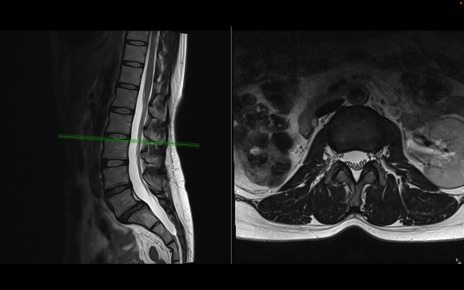

腰椎MRI

T2WI(横断像)

T2WI(矢状断像)